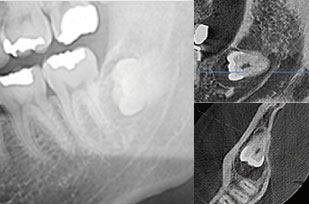

根っこの曲がり方や歯と神経の距離をしっかり把握し、安全かつ負担の少ない抜歯につなげます。